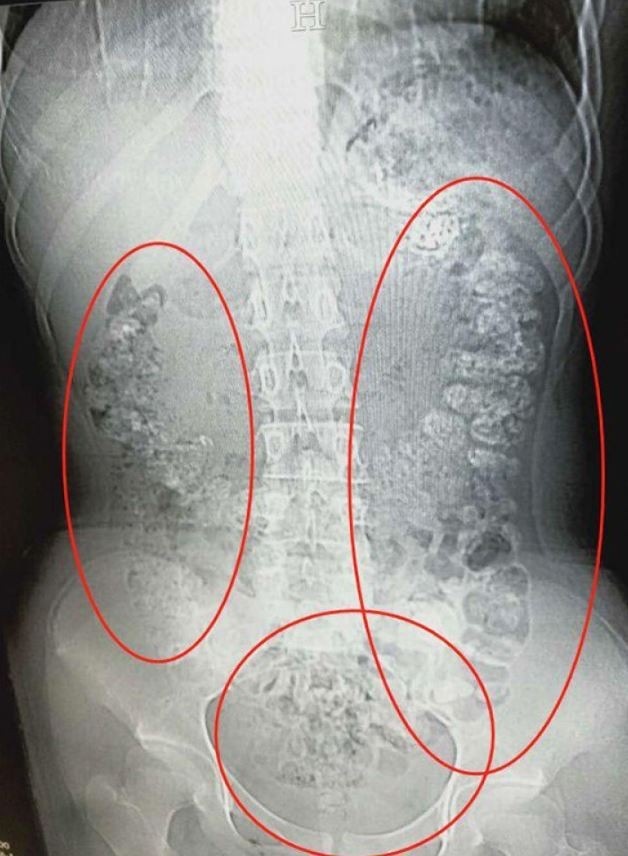

綜合外媒報導,位在中國浙江的14歲少女小沈,因腹痛難耐與便秘5天,在5月28日與父母

一同至浙江諸暨市人民醫院掛急診,張樓煒醫師便馬上安排X光與腹部CT檢查,結果發現

小沈的胃部、橫結腸、升結腸、降結腸、乙狀結腸與肛門口充滿了上百顆顆粒狀陰影。